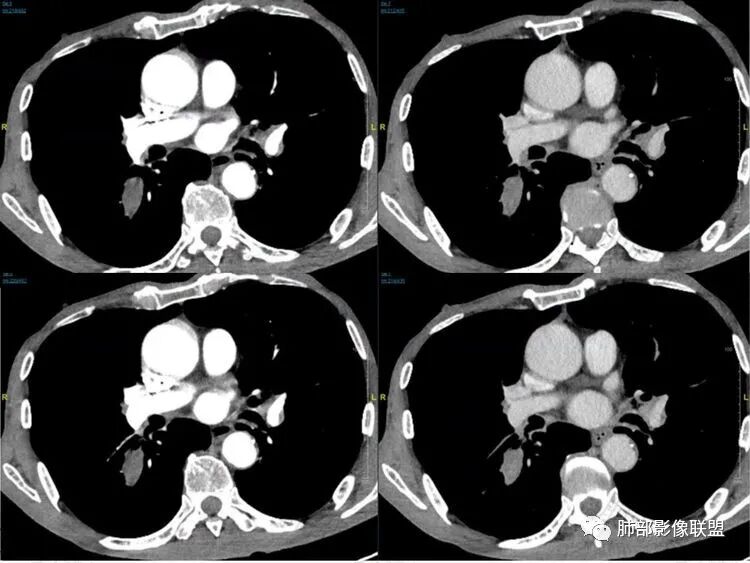

老年男性患者,胸部隐痛1月入院,有长期吸烟史,胸部CT:右肺下叶背段梭型结节灶,边界清晰,无明显分叶、毛刺及周边磨玻璃影,内部密度不均匀,支气管截断,增强扫描不均匀轻度强化,内部似乎见支气管黏液栓,纵隔淋巴结不大,考虑恶性病变:小细胞癌(缺少典型的纵隔肺门淋巴结增大融合),鳞癌(病史复合,但没有阻塞性肺炎,内部没有坏死,),类癌(多见于女性患者,与吸烟关系不大),首先考虑典型类癌,

老年男性,右肺下叶梭形或椭圆形结节,形态较规则,边缘光整,支气管截断,增强不均匀轻度强化,右肺门及纵隔淋巴结增大,考虑恶性病变,鳞癌或小细胞癌,神经内分泌癌(小细胞形)。

老年男性患者,右肺下叶背段梭形结节影,边界比较光整,密度均匀,没有明显的分叶毛刺,没有阻塞性肺炎的表现,这些感觉具备有良性的特点。而近端支气管截断,增强明显的强化,纵隔多发的淋巴结,显得是恶性的特点。总体印象,老年患者+支气管截断征象+明显强化的结节+纵隔多发淋巴结,还是考虑恶性结节,小细胞癌或是鳞癌。

男性,老年人,长期吸烟史,老慢支背景,右下肺背段占位,支气管亚段门口堵,病灶长轴与支气管平行,推测腔内生长可能,病灶内血管穿行,周围干净,轻度强化,右肺门淋巴结肿大,考虑恶性,神经内分泌癌(大小类)>淋巴上皮瘤样癌>腺癌>鳞癌

右肺下叶梭形实性结节,密度均匀,边缘光整,局部膨隆,近端支气管截断,轻度强化,血管走行自然,右肺门及纵隔淋巴结增大,考虑小细胞癌>鳞癌

右肺下叶背段结节,沿着支气管走行呈长椭圆形,边缘圆滑清晰,近端支气管阻塞,远端支气管有沿壁增厚,右肺门淋巴结肿大,中度强化,老年男性,吸烟病史,肺气肿背景,考虑小细胞肺癌,鉴别鳞癌

老年男性,吸烟史,右肺下叶梭形肿块,边缘平直有分叶,支气管近端阻塞,右肺门肿大淋巴结,增强后轻度强化,欠均匀,首先考虑恶性,小细胞肺癌?

老年男性+吸烟+右下肺肿块影+支气管截断+淋巴结肿大,考虑恶性,倾向小

老年男性,吸烟史,右肺下叶背段梭型软组织肿块,边缘膨隆,不均匀强化,近端支气管截断,同侧肺门及纵隔淋巴结肿大,支持恶性,小细胞可能大,鳞癌缺少阻塞性改变

晨读,右下叶梭形占位,边界光滑,支气管截断,可见尾征,不均匀轻度强化,肺门淋巴结肿大,有吸烟史,高龄高危患者,首先考虑恶性,考虑小细胞癌,鉴别一下鳞癌

老年男性,前胸隐痛1月。2年前有白内障手术史。右下肺结节,沿中轴呈梭形,膨隆,边清、无分叶,无毛刺,近端支气管截断完全堵塞,病灶以远未见阻塞性炎症及肺不张。内部密度基本均匀,增强轻微强化,似见局部低密度影。纵隔及右肺门见肿大淋巴结。整体考虑恶性可能性大,小细胞癌?鳞癌?注意鉴别良性结节—错构瘤。

老年男性,长期吸烟史,右肺下叶背段梭形低密度灶,边界清晰,无明显分叶、毛刺,边缘稍彭隆,支气管截断,右肺门淋巴结增大,增强扫描不均匀轻度强化(延迟略明显),首先考虑恶性,小?不典型结核球待排。

右肺下叶背段结节,气管堵塞,密度均匀,边界清晰,无明显分叶、毛刺,边缘膨隆,右肺门淋巴结增大,增强轻度强化,考虑小细胞癌,鉴别鳞癌。

右肺下叶梭形软组织结节,密度均匀,明显尾巴,边缘光整,近端支气管截断,轻度强化,血管走行自然,又腊肠尾巴征象

考虑恶性  小细胞癌?

男,83,前胸部隐痛不适1月。有长年大量吸烟史。胸部CT:肺气肿,右肺下叶纺锤型实性结节灶,边界清晰,支气管截断,内部密度不均匀,增强扫描不均匀强化,右肺门淋巴结大。考虑恶性病变:小?鳞?鉴别炎性肉芽肿、错构瘤等。

晨读:老年男性+吸烟+右肺下叶与气管长轴一致的梭形肿块影+支气管截断,轻度强化,右肺门肿大淋巴结,考虑恶性,小细胞肺癌可能,鉴别鳞癌

呈典型管状改变,近端支气管堵塞、稍扩张,病灶有强化倾向于恶性,没有强化倾向于炎性病变(结核之类);近端呈结节状(鳞癌多一些),这个病例呈管状(小细胞Ca多一些);平扫与强化有差异,有轻度强化,是粘液栓还是血管?